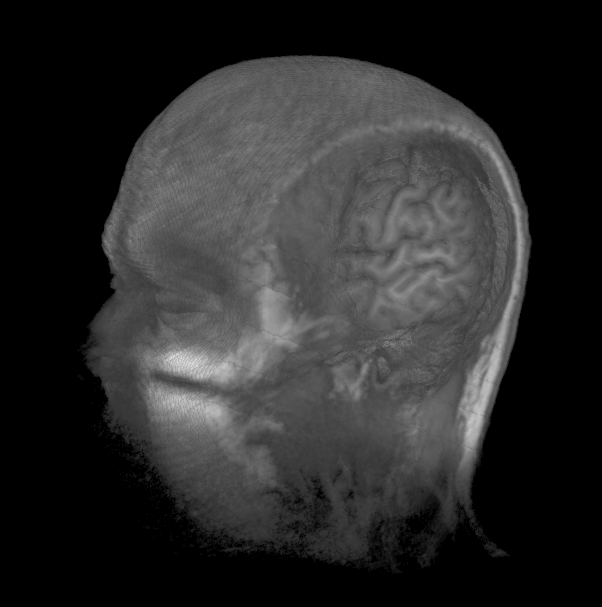

Image Volumes

2D

3D

Marching Cubes creates 3D Meshes

Bill Lorensen 1987